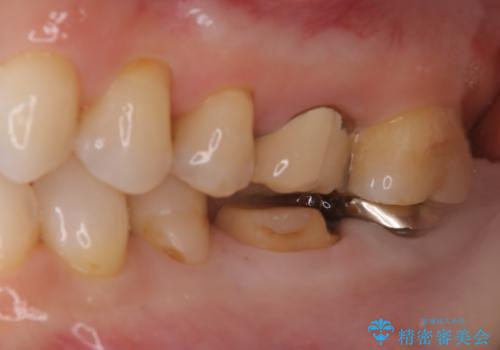

他院で仮歯までしたが、放置していたためセラミック入れたい セラミック治療

- 他院で、仮歯にしたがセラミックの値段が高すぎると思ったため治療相談も含めて来院された患者様です。

仮歯を新調させていただき、再度虫歯治療を行なって、歯の形を作りセラミックを入れさせていただきました。

フルジルコニアクラウン 7万円(税抜)

仮歯 1万円

にて治療させていただきました。色に関しても喜んでいただき満足されていました。